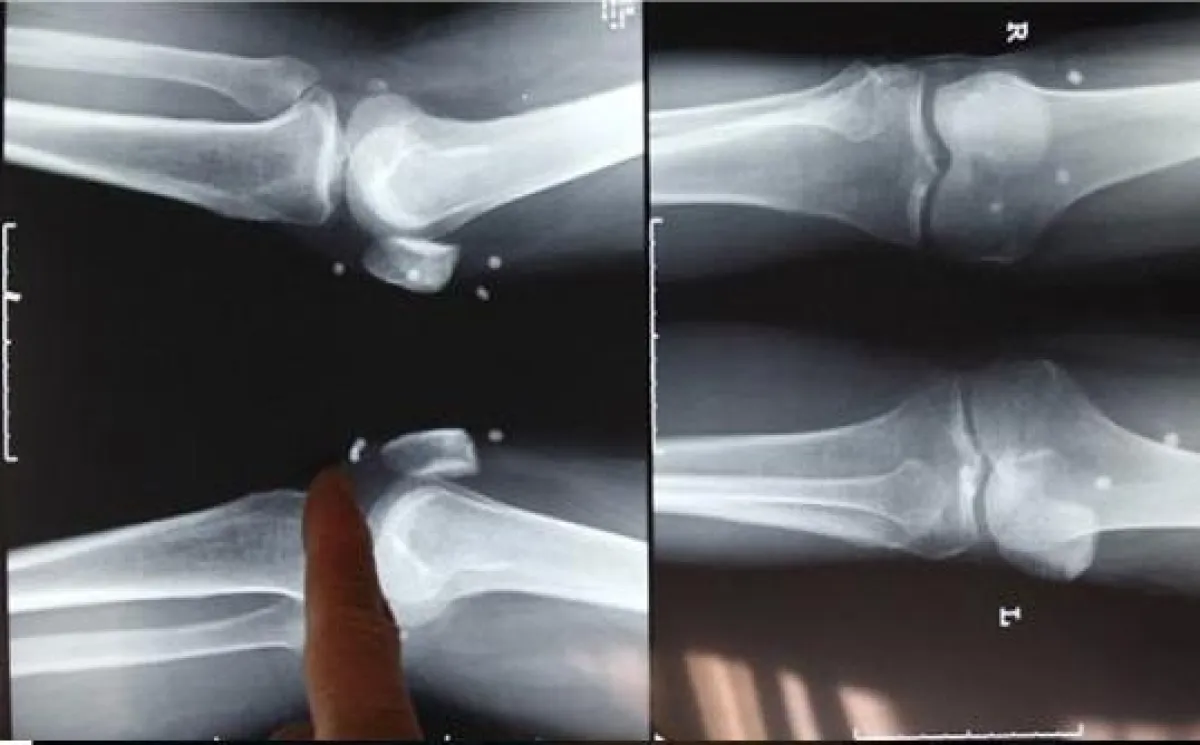

وبعد عامين وجد "فنج" نفسه غير قادر على تحمل الآلام، مما أجبره على البحث عن الطبيب المزعوم غير أنه لم يجده، وهو ما دفعه لزيارة مستشفى متخصص في علاج آلام المفاصل. وبإجراء أشعة سينية على جسد "فنج" تم الكشف عن أماكن زراعة حبات اللؤلؤ، وقد خضع لعملية لاستخراجها غير أنّ الجراح الذي أجرى العملية أكد أنها تسببت في تلف حاد بالهيكل العظمي، ولا سيما مفصل الورك الذي أصبح يتطلب عملية جراحية أخرى لاستبداله.